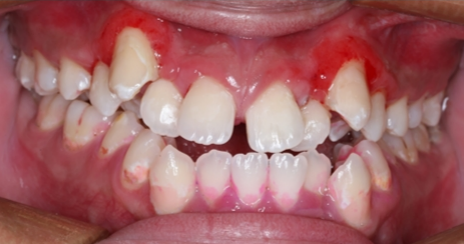

治疗后,小宇的牙齿外观得到了明显改善,龋坏部位被精准修复。3个月后电话回访时,小宇的家属反馈,他的牙齿对冷热酸甜刺激不再敏感,也没有出现新发色素沉着,治疗效果稳定。

治疗后即刻(张晓萌医生提供)